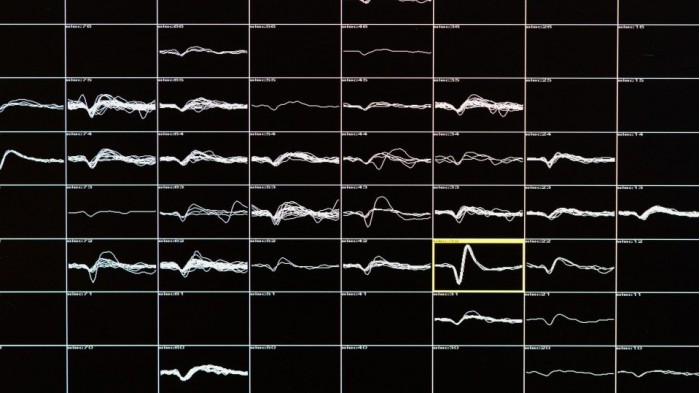

戈麦斯大脑的电信号,每个格子代表一个电极,格子中弯弯曲曲的线条,显示的是来自神经元的信号